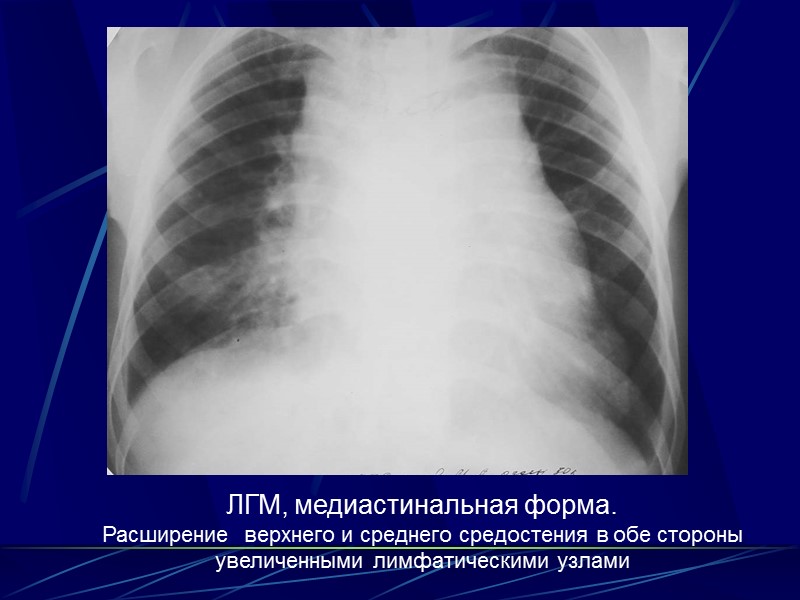

Рентгенологическая семиотика Формы ЛГМ: Медиастинальная Медиастинально-легочная Легочная Медиастинально-легочно-плевральная Плевральная Первые три формы встречаются наиболее часто.

Медиастинальная форма Расширение сердечно-сосудистой тени увеличенными лимфатическими узлами Контуры на стороне поражения четкие, полицикличные, отдельные дуги неравномерно выступают из-за неодинаковой величины л/у Наиболее часто поражаются передне-верхние лимфатические узлы Поражение может быть односторонним или двухсторонним

При двухстороннем поражении срединная тень расширена в обе стороны, это картина известная как «симптом трубы». Если увеличенные л/у располагаются на разной глубине, то они образуя полициклические контуры, картину «кулис». Четкость очертаний средостения сохраняется до тех пор, пока имеется капсула увеличенных узлов. При прорастании гранулема переходит на окружающие ткани и четкость контуров стирается

ЛГМ, медиастинальная форма. Расширение верхнего и среднего средостения в обе стороны увеличенными лимфатическими узлами